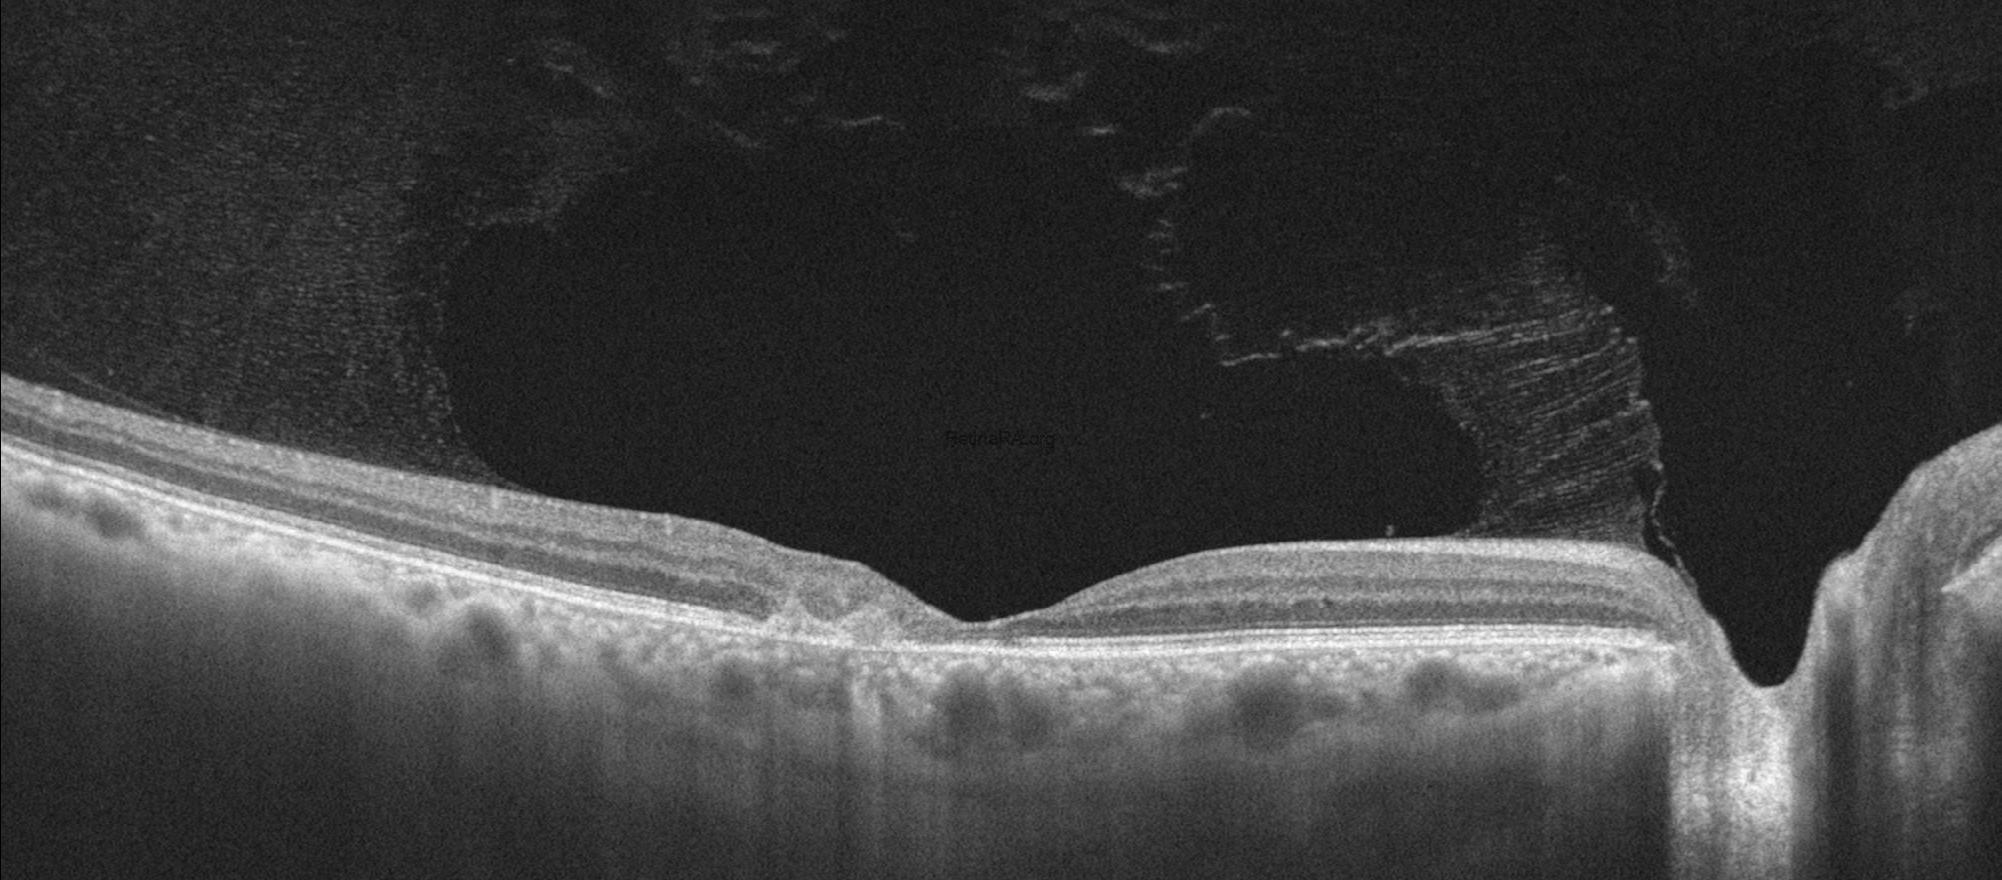

Optical coherence tomography (OCT) demonstrated characteristic parafoveal structural alterations, choroidal neovascularization in both eyes, and Henle fiber layer hemorrhage in the left eye. Early findings include inner and outer retinal cavitations, particularly involving the inner nuclear and outer plexiform layers, often without significant retinal thickening. Disruption and attenuation of the ellipsoid zone are observed in the temporal parafoveal region, reflecting photoreceptor damage. Thinning of the neurosensory retina and loss of normal foveal contour become evident. In the neovascular stage, OCT reveals subretinal hyperreflective material consistent with choroidal neovascularization, frequently accompanied by subretinal fluid, intraretinal cystic changes, and focal retinal thickening.

On optical coherence tomography angiography (OCTA), the superficial capillary plexus typically shows mild capillary rarefaction with dilated and right-angled venules, predominantly in the temporal parafoveal region.

The deep capillary plexus demonstrates more pronounced abnormalities, including telangiectatic and ectatic vessels, capillary dropout, and disorganization of the vascular network, which represent the hallmark vascular changes of MacTel type 2.

In the avascular (outer retinal) slab, the presence of a pathologic flow signal indicates subretinal neovascularization, appearing as a tangled, irregular vascular complex extending from the deep plexus into the outer retina. This neovascular network is often better delineated on OCTA than on conventional angiography and correlates with exudative changes observed on structural OCT.

The patient’s imaging findings after three doses of anti-VEGF therapy are shown below. Visual acuity impoves after treatment to 0.5/0.4.Crystalline deposits are more prominent on color photography of the right eye after anti-VEGF treatment.

After the patient is treated with anti-VEGF injection, disorganization or intraretinal fluid and subretinal exudative fluid findings are resolved and the patient’s acuity returns to baseline.